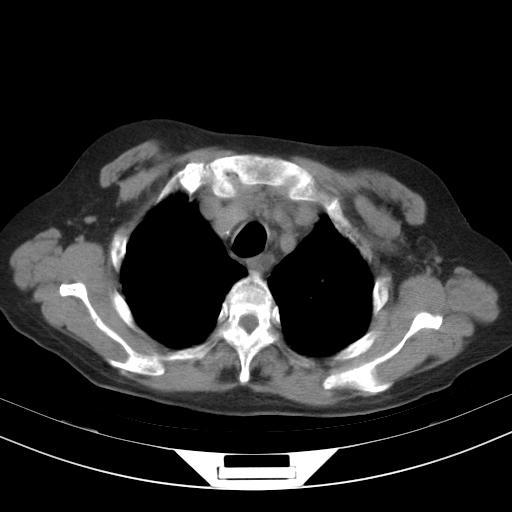

老年女性,嗜睡3天,意识模糊。轻咳,无发热。

两肺慢支炎伴感染,左侧胸腔积液。纵膈及双侧肺门淋巴结肿大建议复查。

1)两肺感染性病变;建议抗炎治疗后复查。2)纵隔淋巴结肿大。3)左侧胸腔积液。